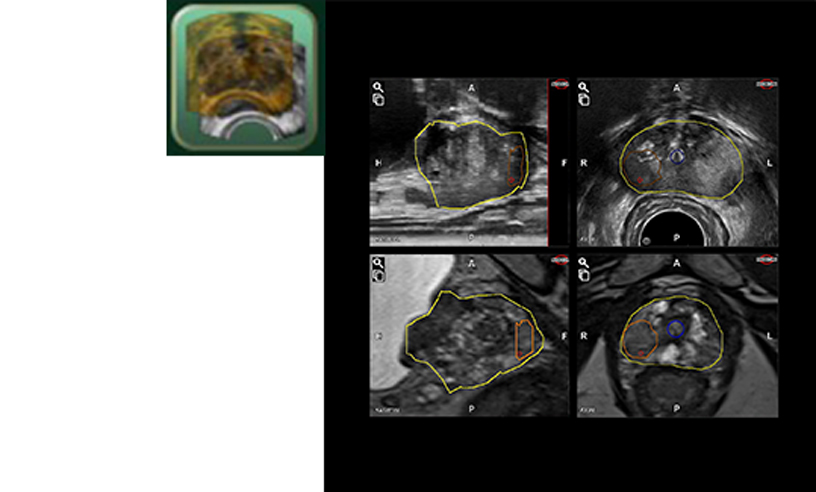

Konturlama Modülü

Çeşitli izleme yöntemleriyle basit konturlama

3D ABD Satın Alma Modülü

Gerçek zamanlı Hız göstergesi, uygun 3D Ultrason Hacmi verisinin alınmasına yardımcı olur.